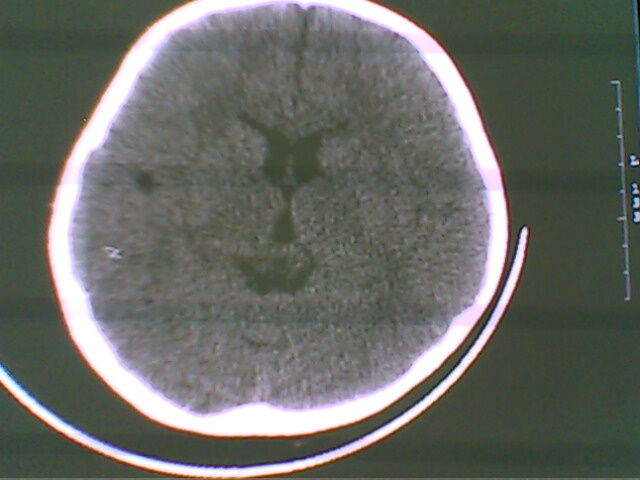

未见明显异常

未见异常

未见明显异常。

无异常发现.

图像有点差,未见明显异常。

正常.

未见明确异常。

图像稍稍有点差,未见明显异常。